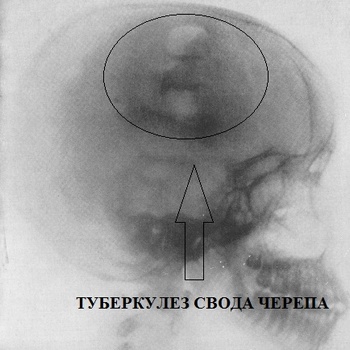

Медицинские аспекты заболеваний: рентгенологическая картина туберкулеза костей

Раздел: Снимки-откровения